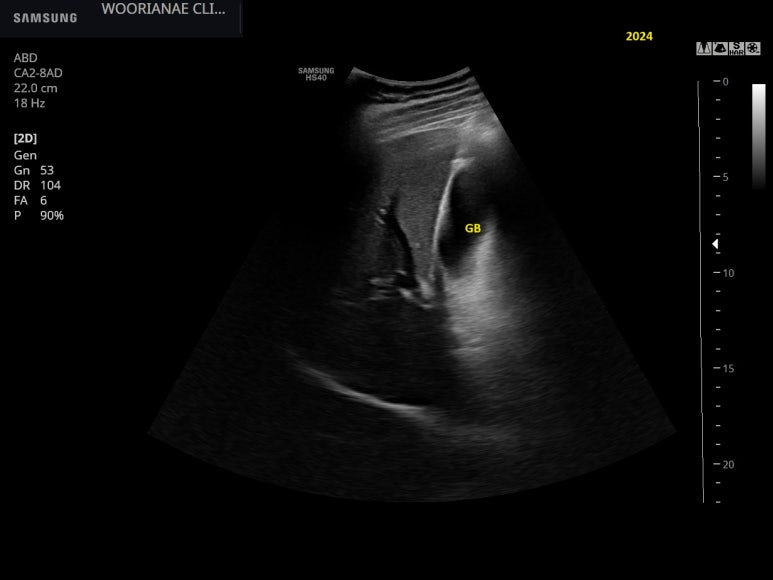

이번엔 담낭내 찌꺼기... 오니 혹은 결과로서 담낭수종의 모습이다.

S; sludge, B; bile

췌장 두부의 총담관도 경도로 늘어나 있다. sludge가 여기까지?

담낭 목의 관찰, 뚜렷한 담석은 없으나 담낭내 지저분한 음영